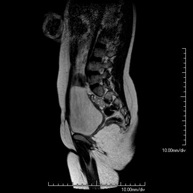

Prueba diagnóstica no invasiva que consiste en la obtención de imágenes de alta definición anatómica de la columna dorsal, mediante el empleo de un campo electromagnético y ondas de radio (con un emisor y un receptor). No utiliza radiación ionizante. Indicaciones: traumatismo, problemas degenerativos, hernias, tumores. - RM Columna lumbar

Prueba diagnóstica no invasiva que consiste en la obtención de imágenes de alta definición anatómica de la lumbar y sacra, mediante el empleo de un campo electromagnético y ondas de radio (con un emisor y un receptor). No utiliza radiación ionizante. Indicaciones: traumatismos, ciática, hernias discales, tumores, infecciones. - RM Mielografía